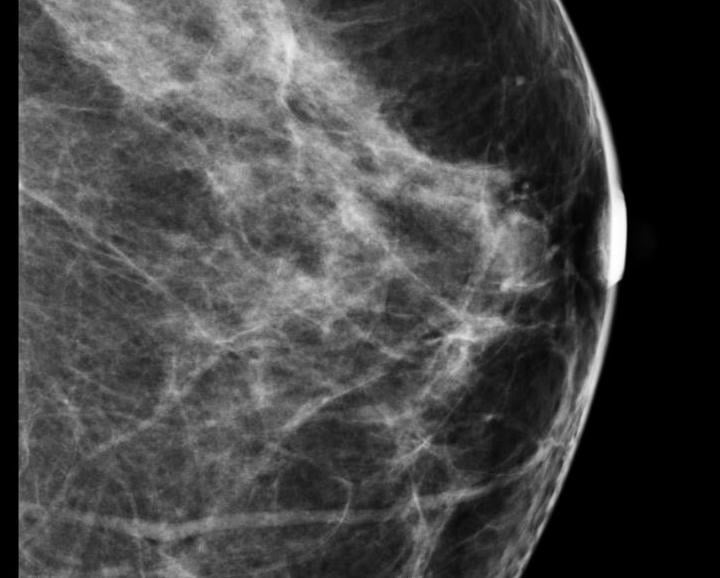

Looking for signs of cancer in the mammogram of a dense breast is like looking for a polar bear in a snowstorm. Because they absorb X-rays, glandular and fibrous tissue appear white, as do microcalcifications, lumps and other lesions that may indicate breast cancer.

Despite decades of progress in breast imaging, one challenge continues to test even the most skilled radiologists ...

The practice of breast imaging and screening in women at risk for breast cancer is evolving as new imaging modalities are incorporated and researchers continue to study the implications of dense breast tissue in patients. At the 2013 annual meeting of the Radiological Society of North America (RSNA) in Chicago, there were several sessions highlighting trials and studies that brought breast density and cancer detection to the forefront.

St. Peter’s Breast Center, located in Albany, N.Y, added 3D mammography (breast tomosynthesis) in 2011 because the staff knew it would improve diagnostic accuracy; even so, the technology has exceeded all expectations. In 2012 more than 22,000 mammograms were performed at the breast center.

To help identify trends and find out what topics Imaging Technology News (ITN) readers are interested in, our editorial team makes note of what the audience is viewing online at itnonline.com. In 2013, the topic of women’s breast health — specifically, breast density — dominated half of this list. Perhaps 2014 will be the year that standardized breast density reporting will become law in all states; 2013 got this off to a good start, helping to spread awareness. Other hot topics included healthcare reform and the role it could play in the radiology field, and of course breaking new technology.